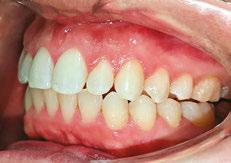

Patient J, a 39-year-old female, (Figures 1, 2, 3, 4, 5, 6) came to the office with concerns about difficulties chewing food and experiencing dry mouth upon waking up in the morning. Additionally, her partner was disturbed by her snoring. Upon examination, several issues came to light:

1. An open bite in the anterior region and a posterior crossbite

2. Breathing through the nose 10% of the time.

3. Lips and cheek muscles actively helping with swallowing food and drinks

4. Lips open 100% of the time

5. Tongue cannot maintain position on a spot, moves between teeth upon swallowing

6. Tongue thrust

7. Weak control over soft palate

Muscle tension around the temporomandibular joint (TMJ) was also evident5 as well as mandibular bilateral lingual torus as response to constant occlusal pressure applied during bruxism.

Figures 3 and 4: 3. Right side before treatment. 4. Left side before treatment